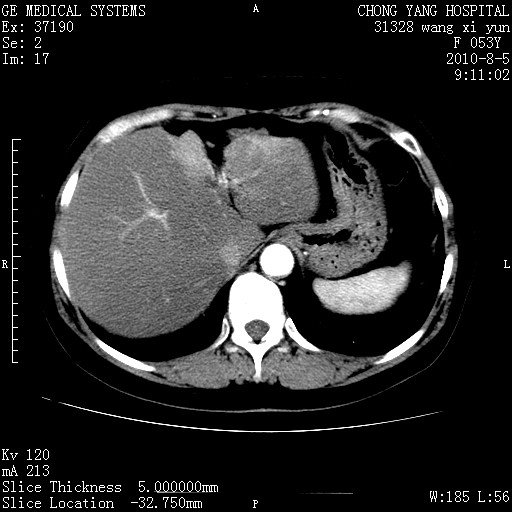

标题: CT28214:F41Y 血尿二十天,建议盆腔平扫加增强。

胆管细胞ca?

1)考虑肝左叶胆管细胞癌。2)脂肪肝。

支持胆管细胞ca。